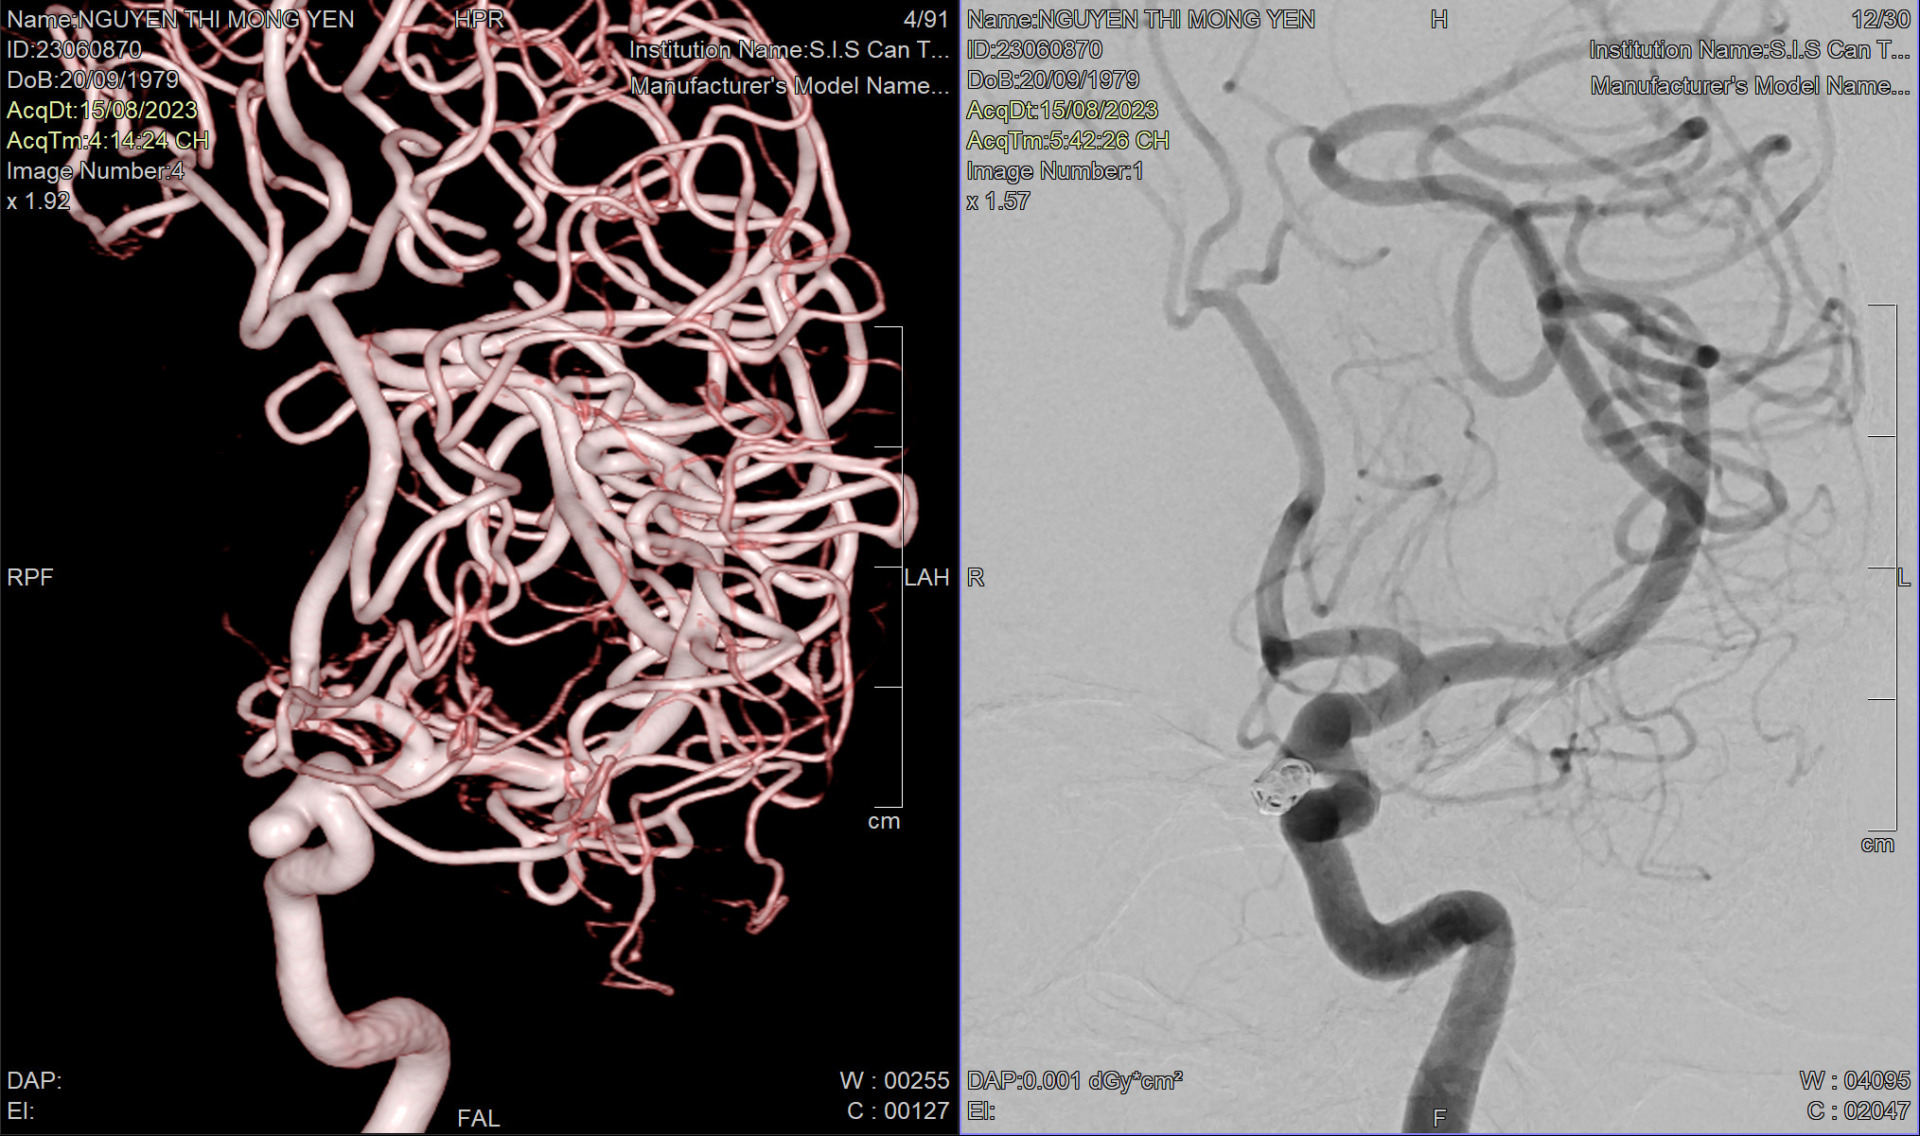

Bệnh viện S.I.S Cần Thơ can thiệp thành công ca bệnh túi phình kèm bệnh lý giảm tiểu cầu với chi phí chưa tới 100 triệu đồng

Đứng trước 270 triệu tiền phẫu thuật điều trị phình động mạch cảnh trong, nữ bệnh nhân cầu cứu thông qua truyền hình. Cuối cùng, được S.I.S Cần Thơ tiếp nhận và cấp cứu thành công với chi phí thấp hơn hơn một nửa.